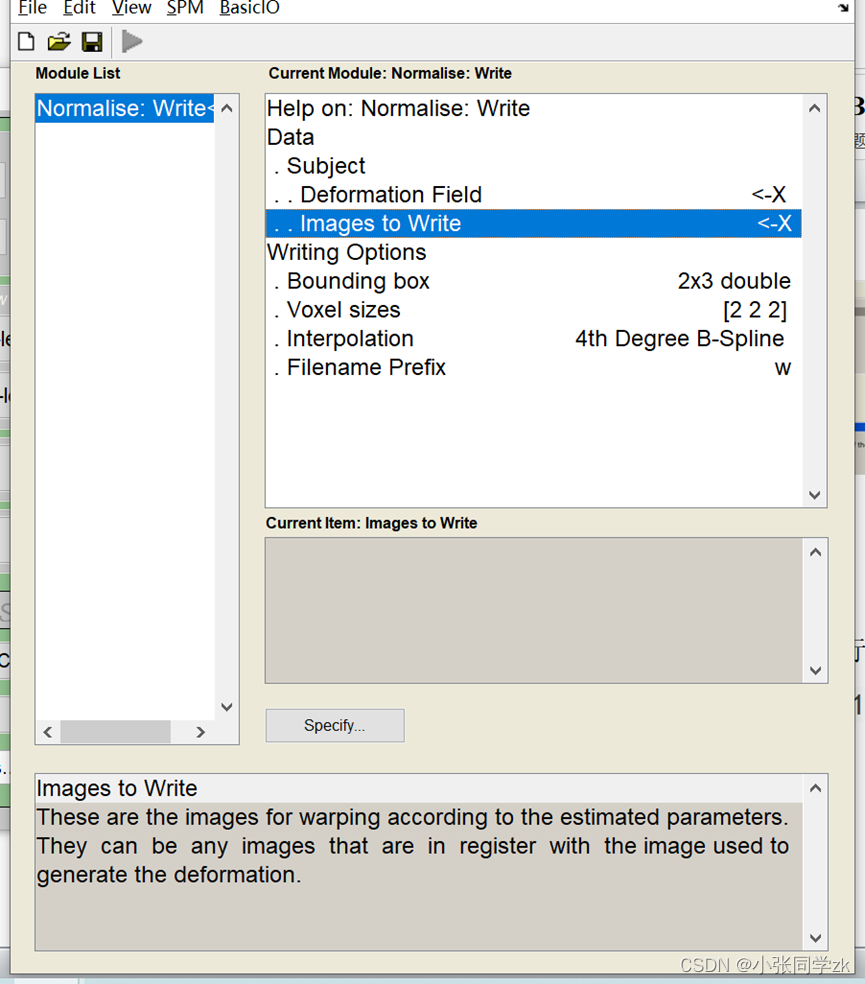

3.5 Normalization

当结构像被分割之后,我们可以利用分割之后的结构像进行标准化。点击Normalize (Write),→data,创建一个新的subject,在Deformation Field这一栏中载入anat文件夹中的 y_rsub-08_T1w.nii文件,在Images to Write 这一栏中加入头动矫正和时间层之后的数据,为了提高效率在Filters中输入^ar.* ,1:146 。默认的图像大小是2×2×2大小的高分辨率图像,我们可以更改为大小为3×3×3的图像。

!note

我们可以选择头动矫正后的结构像进行归一化,这样我们就可以看到单个被试归一化之后的结构像。

这一步完成之后,我们需要检查一下是否出错,点击Check Reg,找到w开头的功能像文件,对于第二个image,找到spm12/canonical 工作路径下的T1或者avg152T1.nii, avg305T1.nii, or single_subj_T1.nii图像,检查是否配准的好。